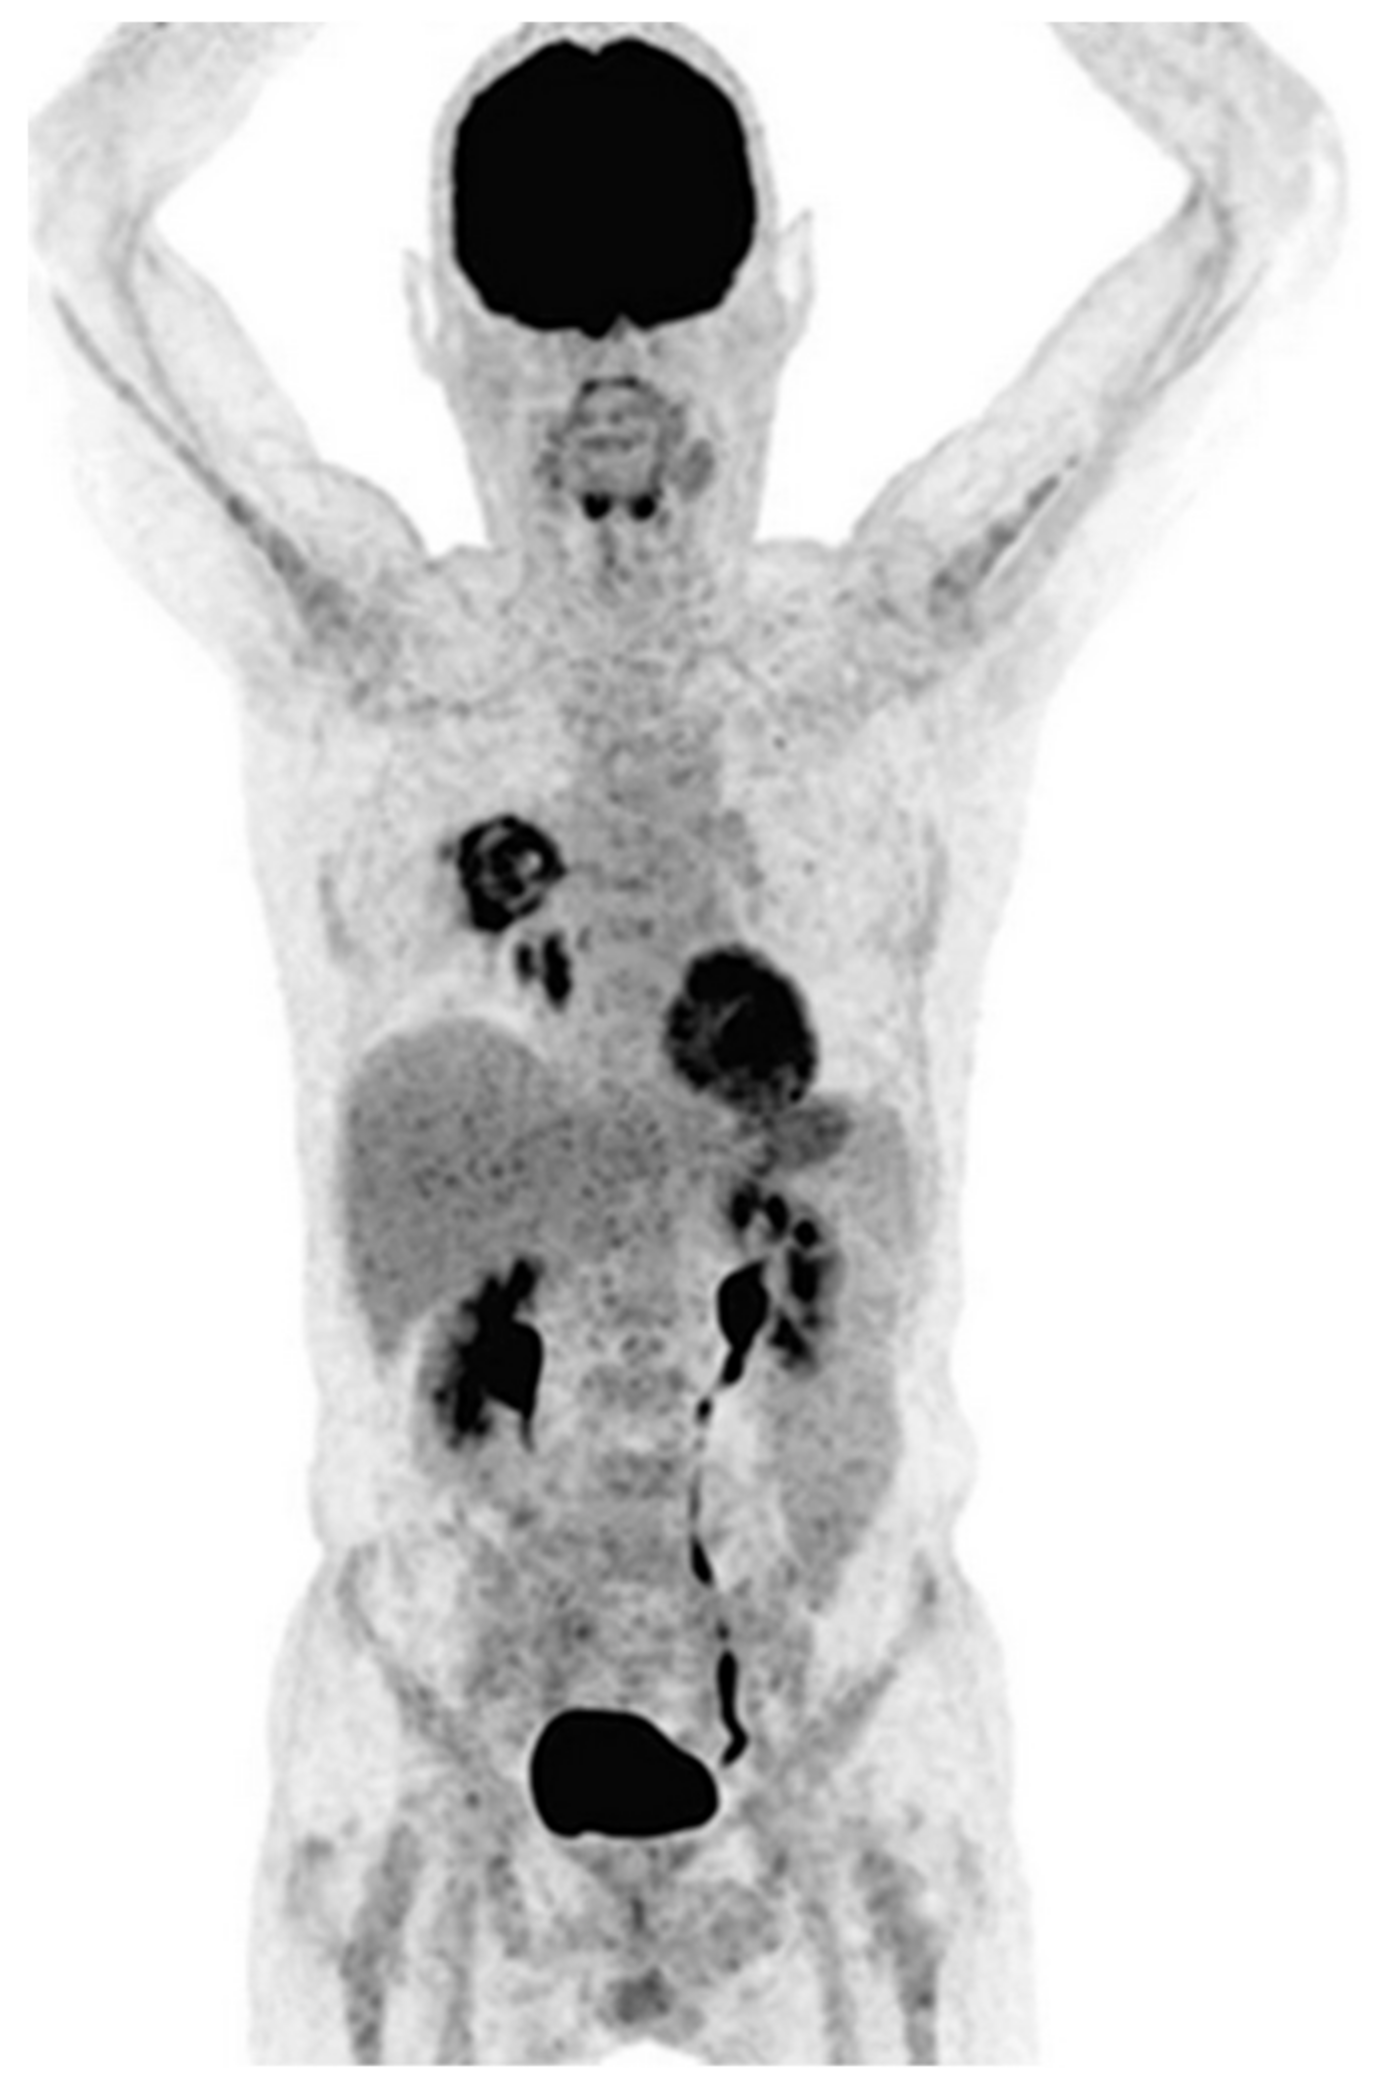

- Sharma, P.; Mukherjee, A.; Karunanithi, S.; Bal, C.; Kumar, R. Potential Role of18F-FDG PET/CT in Patients With Fungal Infections. Am. J. Roentgenol. 2014, 203, 180–189. [Google Scholar] [CrossRef]

- Hot, A.; Maunoury, C.; Poiree, S.; Lanternier, F.; Viard, J.P.; Loulergue, P.; Coignard, H.; Bougnoux, M.E.; Suarez, F.; Rubio, M.T.; et al. Diagnostic contribution of positron emission tomography with [18F]fluorodeoxyglucose for invasive fungal infections. Clin. Microbiol. Infect. 2011, 17, 409–417. [Google Scholar] [CrossRef]

- Leroy-Freschini, B.; Treglia, G.; Argemi, X.; Bund, C.; Kessler, R.; Herbrecht, R.; Imperiale, A. 18F-FDG PET/CT for invasive fungal infection in immunocompromised patients. QJM Int. J. Med. 2018, 111, 613–622. [Google Scholar] [CrossRef]

- Ankrah, A.O.; Span, L.F.R.; Klein, H.C.; de Jong, P.A.; Dierckx, R.A.J.O.; Kwee, T.C.; Sathekge, M.M.; Glaudemans, A.W.J.M. Role of FDG PET/CT in monitoring treatment response in patients with invasive fungal infections. Eur. J. Nucl. Med. Mol. Imaging 2019, 46, 174–183. [Google Scholar] [CrossRef] [PubMed]